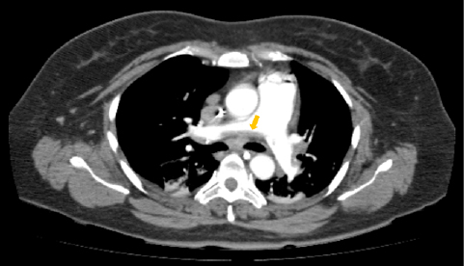

Radiología intervencionista decide realizar embolización, posicionándose stent en cuello de aneurisma, con colocación de 5 coils de 2x10 mm en su interior. Al realizar control angiográfico, se observó la presencia de múltiples elementos radiolúcidos en relación con trombos en posición proximal del stent, por lo que se administró bolo IV de alteplasa de 20 mg y se continuó con 50 mg en infusión continua por 24 horas, trasladándose a Unidad de Cuidados Intensivos (UCI), donde ingresa con choque de posible origen neurogénico (dado el evento presentado) y se inicia manejo de su choque y neuroprotección bajo ventilación mecánica invasiva y sedación profunda (con RASS meta de -5 puntos) con fentanil, midazolam, y soporte vasopresor con norepinefrina. En la TAC de cráneo simple, se observó hipodensidad cortico-subcortical con compromiso fronto-parieto-temporal izquierdo, de etiología vascular isquémica, asociada a edema perilesional con cierre ventricular completo (Figura 1), adicionándose al manejo manitol al 20 % y fenitoína. Desde el ingreso a UCI recibió tromboprofilaxis con medias antiembólicas. Evolución tórpida, persiste con inestabilidad hemodinamica, y adicionalmente presenta disminucion súbita y severa en índices de oxigenación (PaO2/FiO2 = PaFi de 101.2, con valores previos de PaFi mayores de 250) sin alteración en reactantes de fase aguda, ni fiebre, por lo anterior se sospecha embolia pulmonar de alto riesgo y se solicita TAC de torax con protocolo para TEP la cual reportó múltiples defectos de llenado bilaterales a nivel de las arterias pulmonares y sus ramas segmentarias, con evidencia de trombo a nivel de bifurcación del tronco de la arteria pulmonar (Figura 2), hallazgo que coincide con tromboembolismo pulmonar de alto riesgo, dada la repercusión hemodinámica. (PESI score de 155 puntos).

Figura 1. Isquemia cerebral con gran compromiso hemisférico izquierdo y edema perilesional. Fuente: Departamento de radiología, Hospital Universitario de Santander.